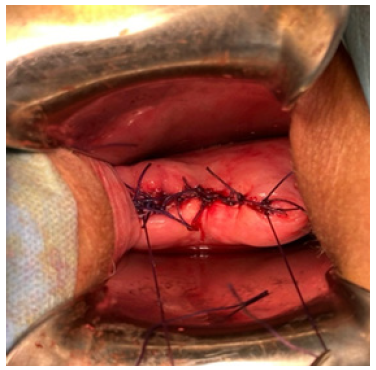

A.S, a 45-year-old woman, has a history of two vaginal deliveries and a Transobturator Tape (TOT) procedure performed 10 years ago for urinary incontinence; she has no other illnesses, allergies, or history of medication use; her body mass index is 27, and she smokes 1.5 packs of cigarettes per day. The patient underwent TLH (Total Laparoscopic Hysterectomy) and Bilateral Salpingectomy due to abnormal uterine bleeding, with preoperative pathology tests revealing benign results. During the operation, the vaginal cuff was circumferentially cut from front to back using a monopolar hook, and the vaginal cuff was sutured with 2.0 V-loc. Postoperative follow-ups were uneventful. 1.5 months after the operation, she presented to the gynecology clinic with complaints of bloody vaginal discharge, a sensation of pressure towards the vagina, and lower abdominal pain following coitus. On speculum examination, a 3x3 cm prolapsed mass from the vaginal cuff and minimal vaginal bleeding was observed (Figure 1). Vital signs were stable, together with an unremarkable abdominal examination. Her bowel sounds were also found to be normoactive on auscultation. Vaginal ultrasonography showed a solid mass above the cuff, with no evidence of bowel prolapse (Figure 2). Laboratory tests, including hemogram and biochemical studies, were normal. The patient was thus admitted to emergency surgery for transvaginal cuff repair due to suspicion of vaginal cuff dehiscence and omental prolapse. Peroperatively, the omentum was reduced back into the abdomen via vajinal route in trandelenberg position (Figure 3). Upon further examination the vaginal cuff was found to be partially necrotic. Single interrupted sutures with 0 Vicryl were placed in a 4cm long dehisced cuff (Figure 4). No issues were detected during the 1st week and 2nd-month postoperative follow-up.